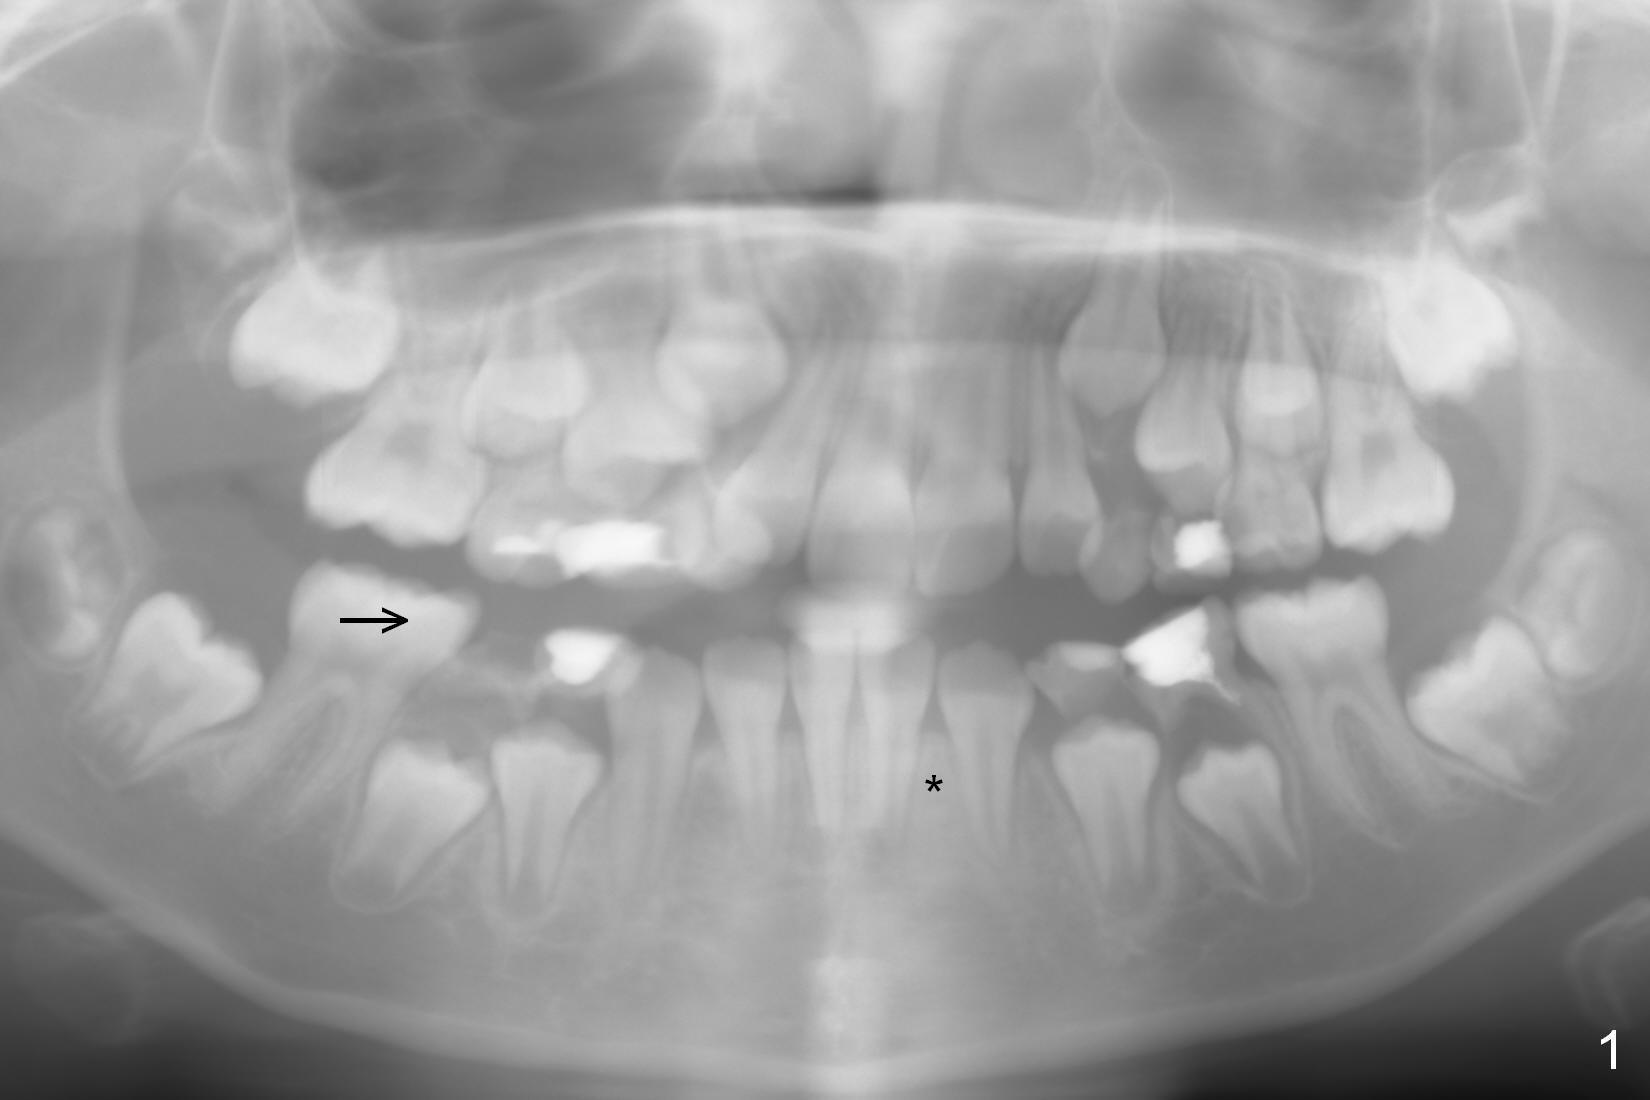

A 9-year-old girl has 2 space issues (missing #26 (*) and mesial shift of #30 (arrow), Fig.1). After extraction of S and T (Fig.2), a space regainer is fabricated. In 3 months, the tooth #28 is erupting (Fig.3); the regainer is being activated. Next visit, check anterior overjet. When the regainer is activated, the tooth #27 feels being pressured. The lower anterior teeth may be pushed anteriorly.